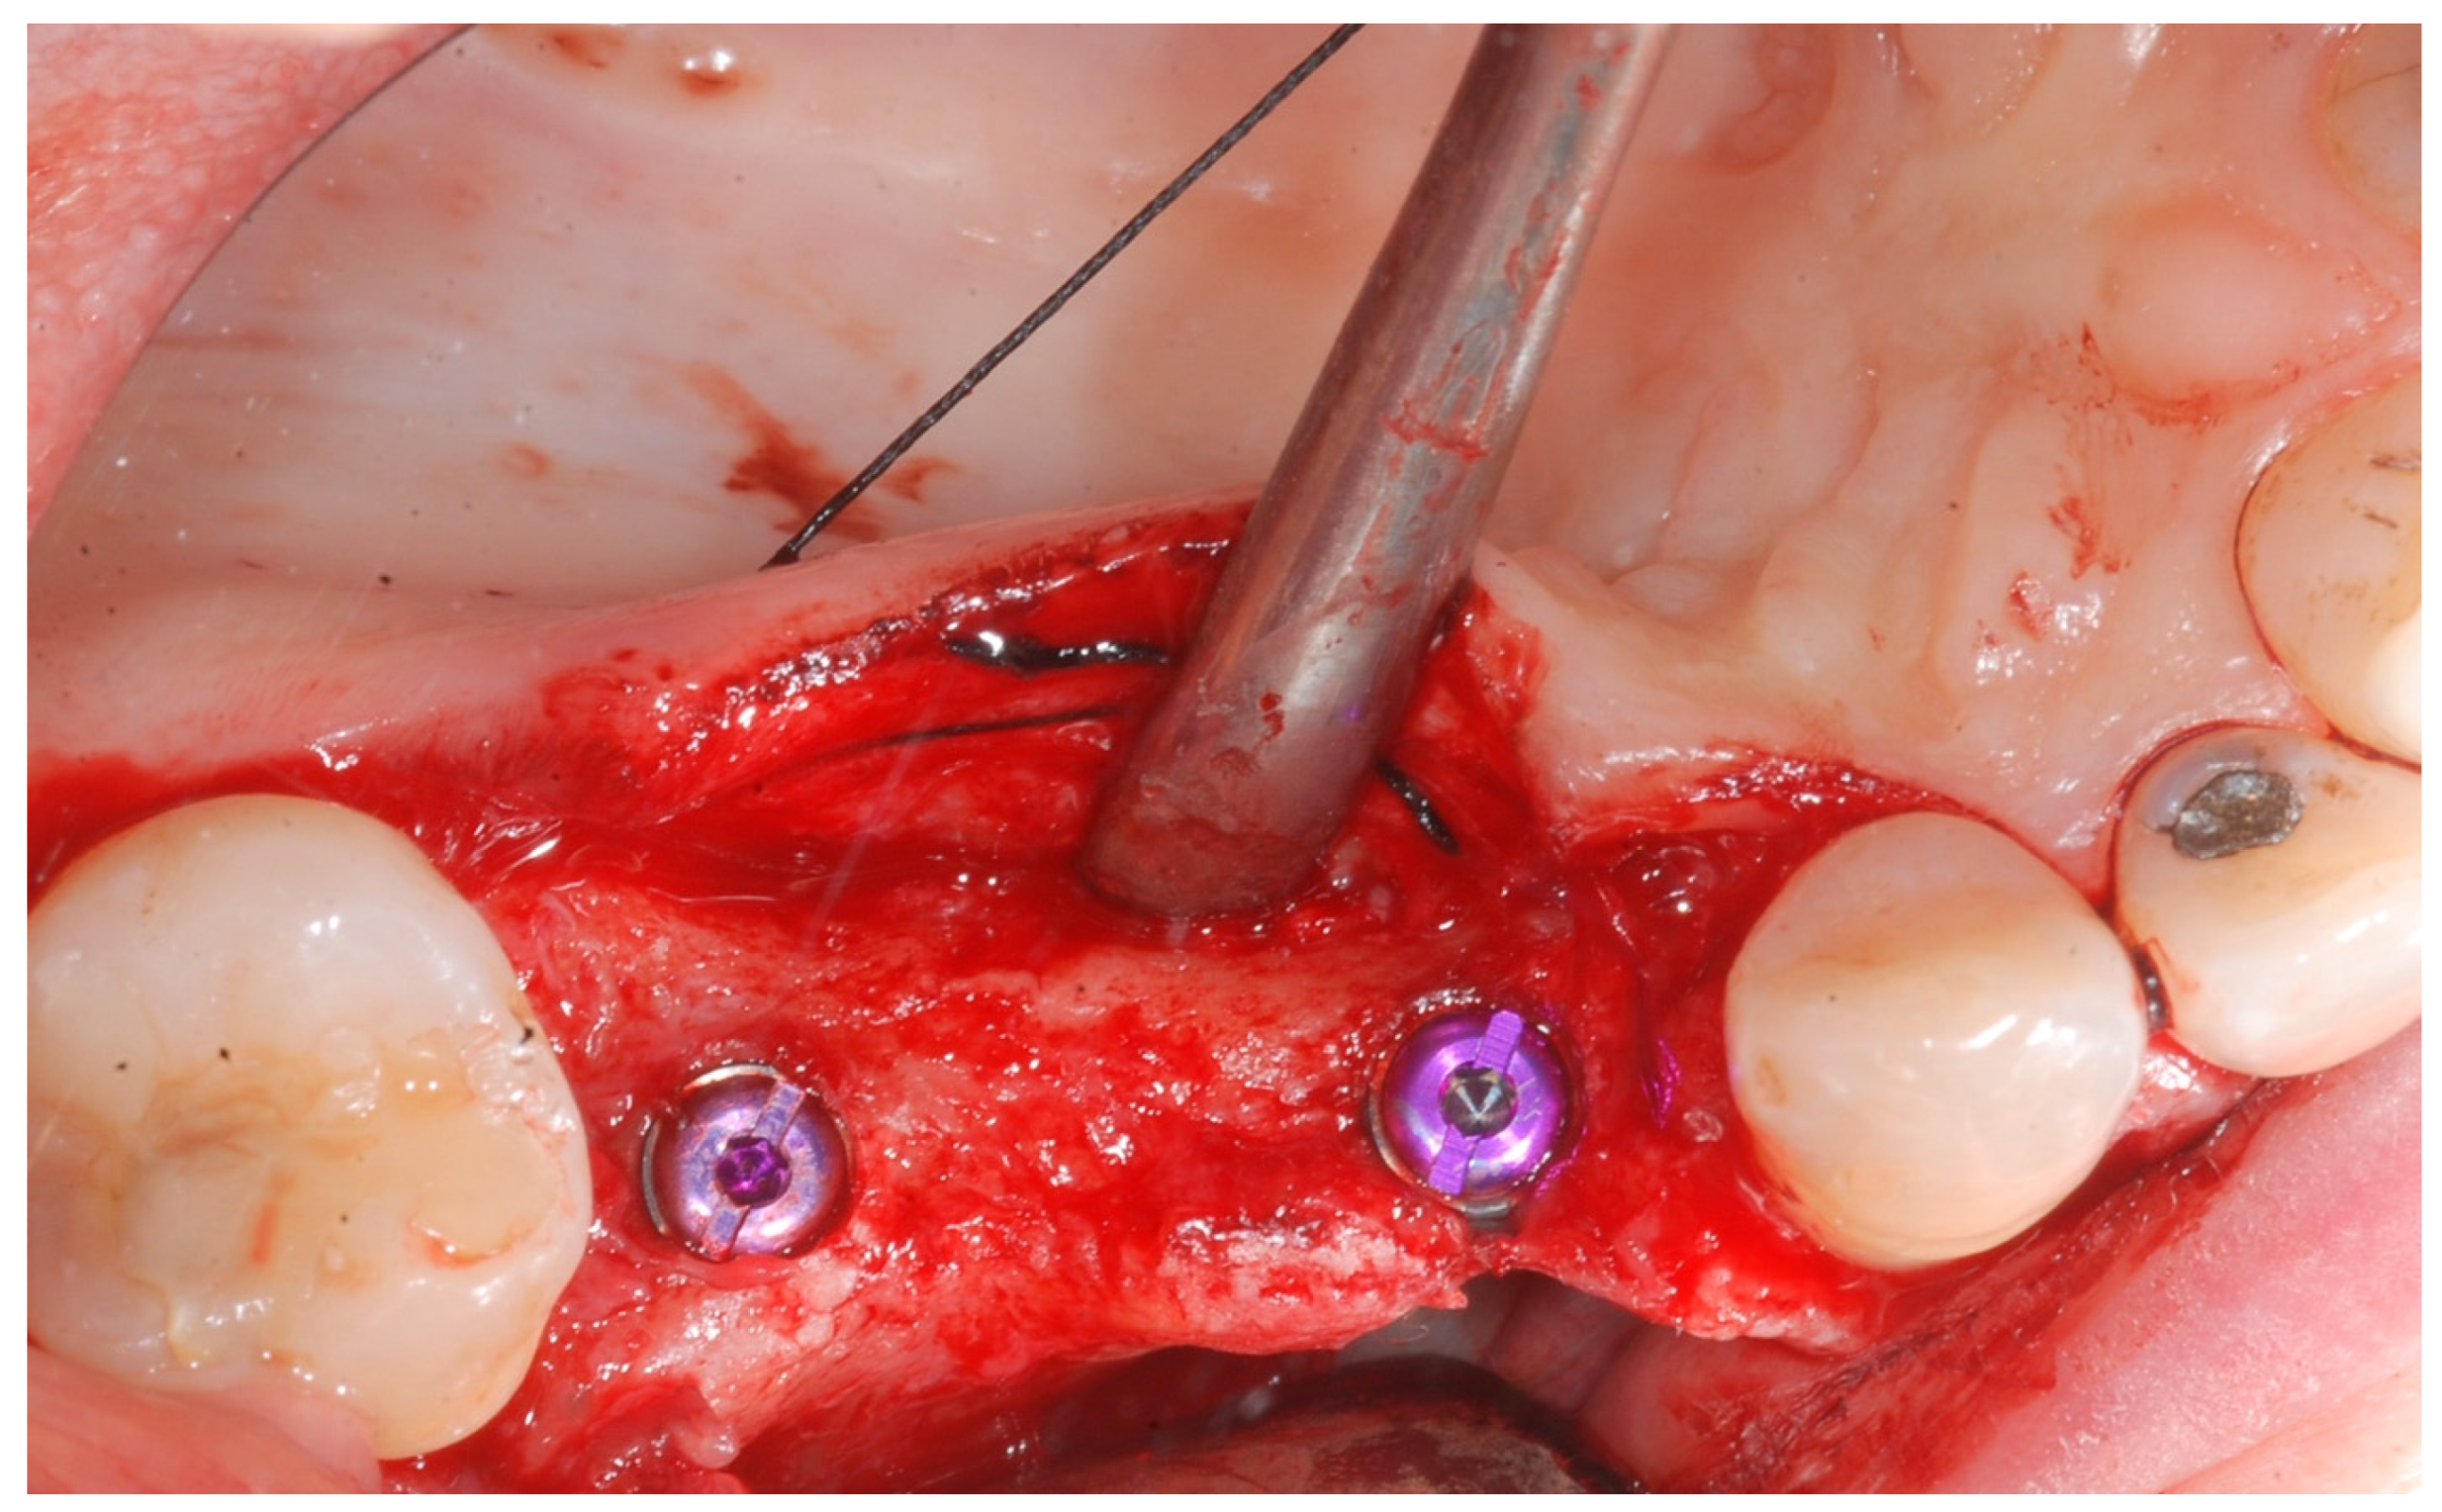

Local anesthesia was obtained with mepivacaine 20 mg/mL with epinephrine 1:100.000 (Optocain, Molteni Dental, Milan, Italy) injections. To raise a mucoperiosteal flap, a crestal incision followed by oblique releasing incisions were made to allow for a wide flap basis as well as sufficient access to the defective ridge area. The flaps were carefully raised using tissue elevators. The bone ridge was examined and any soft tissues remaining on the crest were meticulously removed with a surgical curette (Figure 2).

At this point, implants were placed according to the manufacturer’s instructions in a prosthetically ideal position with the aid of the surgical stent (Figure 3 and Figure 4).

The cortical bone plate was perforated at numerous locations using a round bur in order to allow access of the cells from the bone and bone marrow to the area of regeneration. Subsequently, granules of cancellous deproteinized bovine bone mineral (DBBM) (Bio-Oss, Geistlich AG, Wolhusen, Switzerland), were placed in the defect area (Figure 5). A collagenous resorbable membrane (T-Gen, HYUNDAI BIOLAND Co., Ltd., 162, Gwahaksaneop 3-ro, Ochang-eup, Cheongwon-gu, Cheongju-si, Chungcheongbuk-do, 28125, Republic of Korea) was shaped and trimmed to cover the graft and to extend 2–3 mm onto the intact bony borders of the defect. The membrane was hydrated and the fixation was accomplished using fixation pins (MC Bio S.r.l., Como, Italy) (Figure 6).

Figure 2. Trapezoidal flap elevation and initial bone thickness.

Figure 4. Implant positioning and cover screws in place.